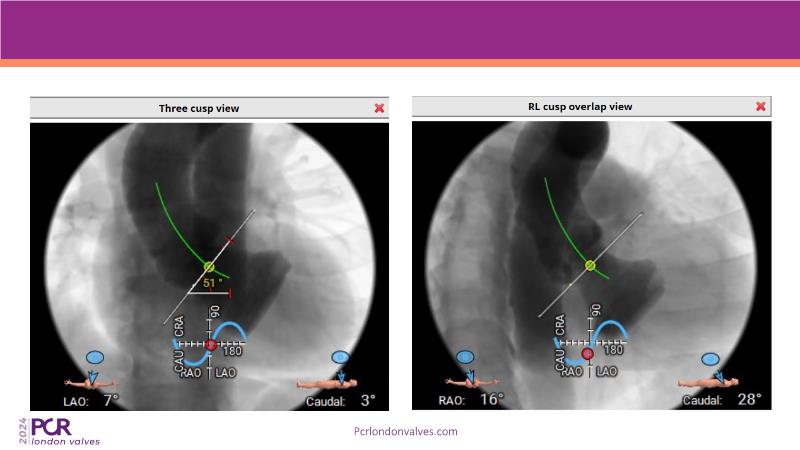

- To learn from the experts best-in-the-class TAVI practice: pre-procedural (Imaging, sizing rationale, treatment strategy), procedural tips and tricks and post-procedural management